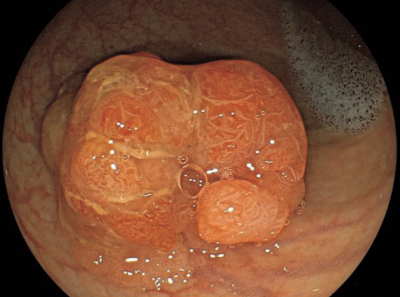

腹部造影CTでは明らかな転移を認めなかった。後日入院し治療が行われた。治療時の下部消化管内視鏡像を別に示す。

この患者に行われたのはどれか。

a. 内視鏡的硬化療法

b. 内視鏡的異物除去術

c. 内視鏡的粘膜切除術

d. アルゴンプラズマ凝固

e. 内視鏡的粘膜下層剥離術